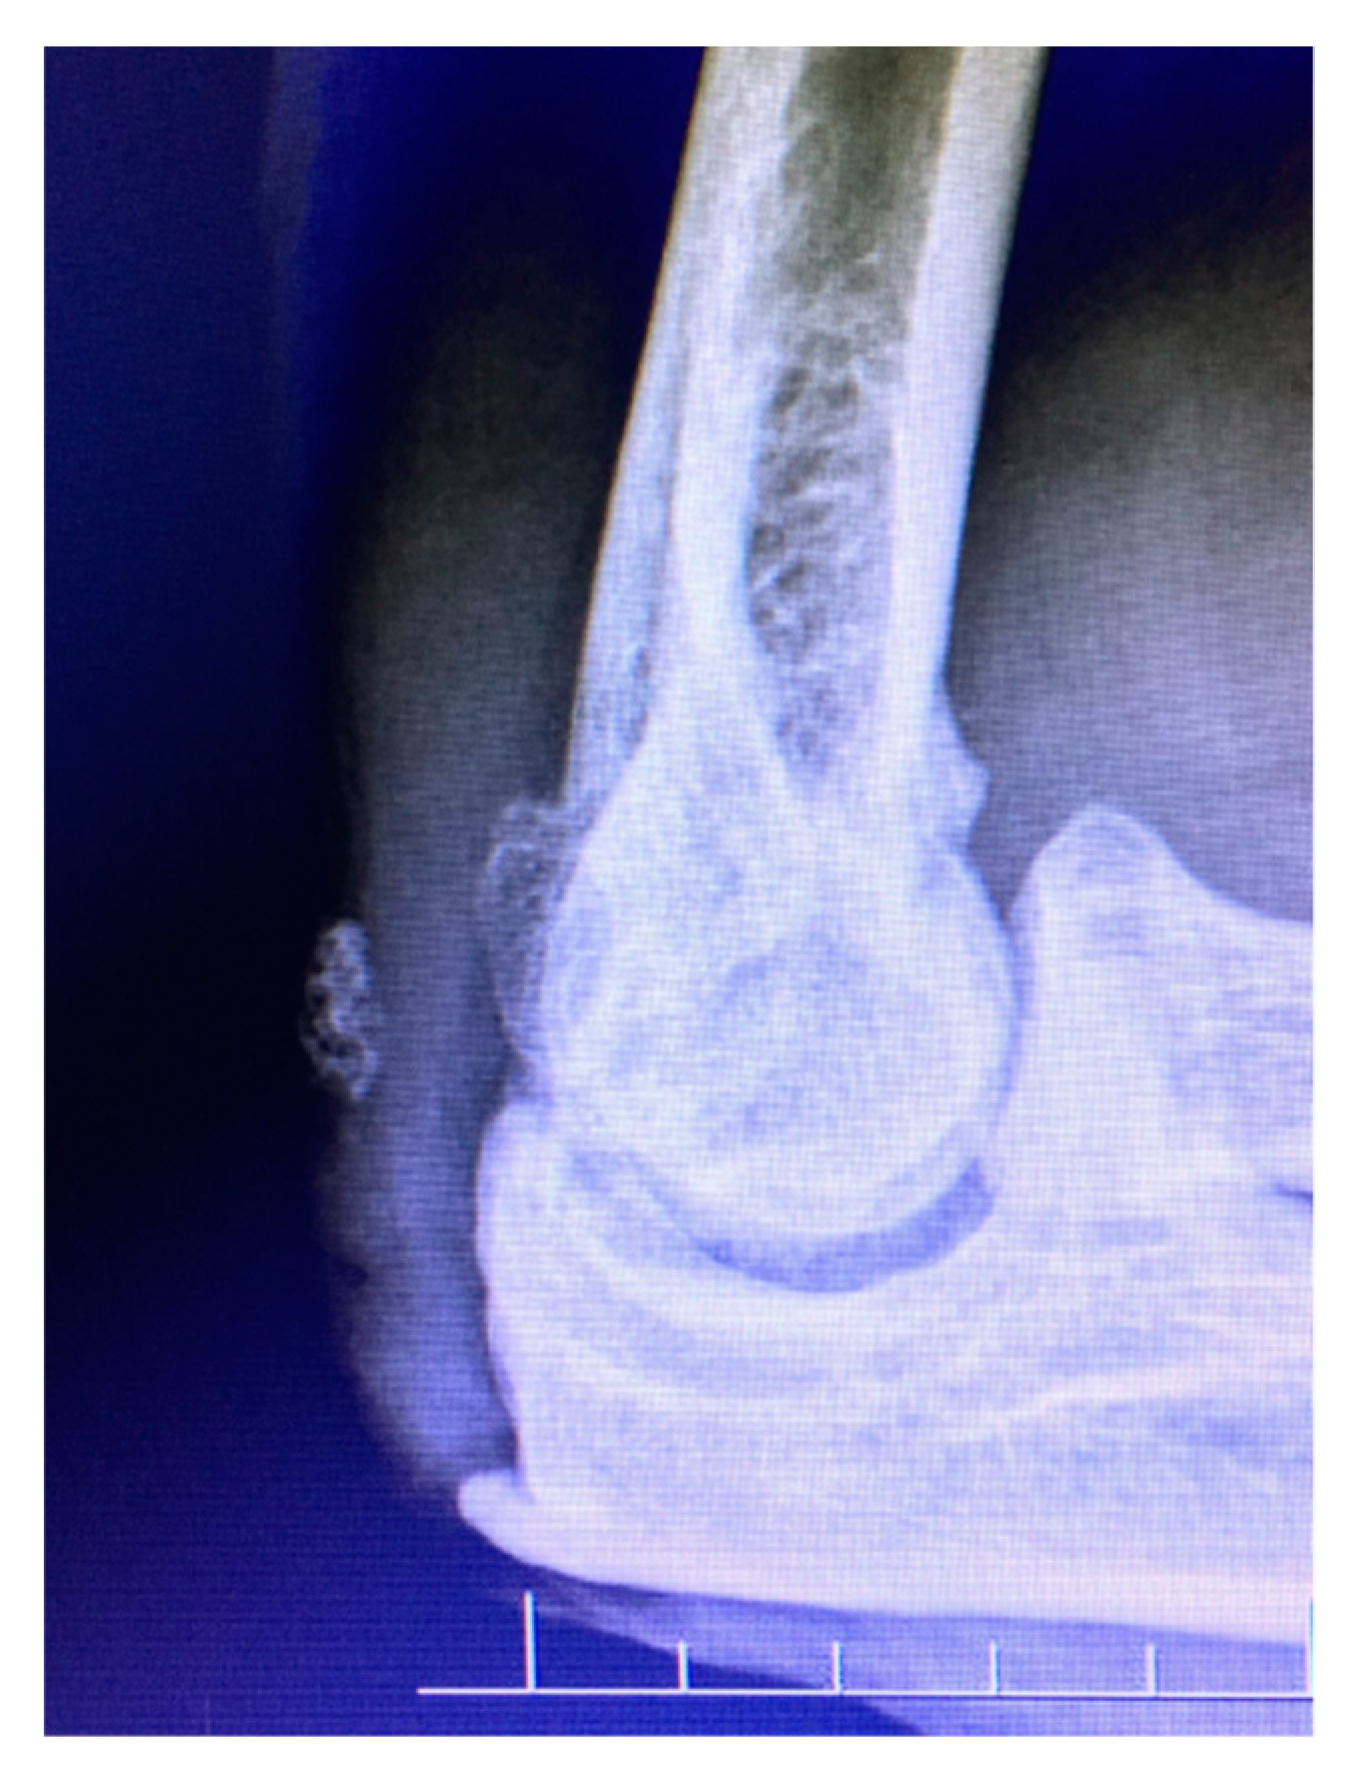

3.3. Imaging

Figure 3.

Lateral radiograph demonstrates idiopathic arthritis with osteophytes on the radial head, as well as anterior and posterior ulno-humeral joints.